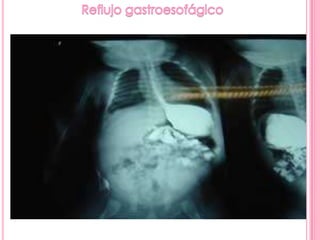

El estudio baritado muestra un esófago dilatado por alteración del peristaltismo y

falta de relajación del esfínter esofágico inferior, que presenta el típico aspecto en

"pico de flauta" (flechas)